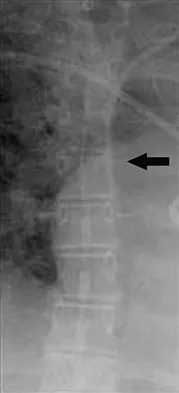

Figures 32a and 32b show the AP and lateral radiographs of an 11-year-old boy who has a severe limp, a fever, and swelling and tenderness of the thigh. Aspiration of the bone reveals purulent material. The patient has most likely been symptomatic for

Explanation